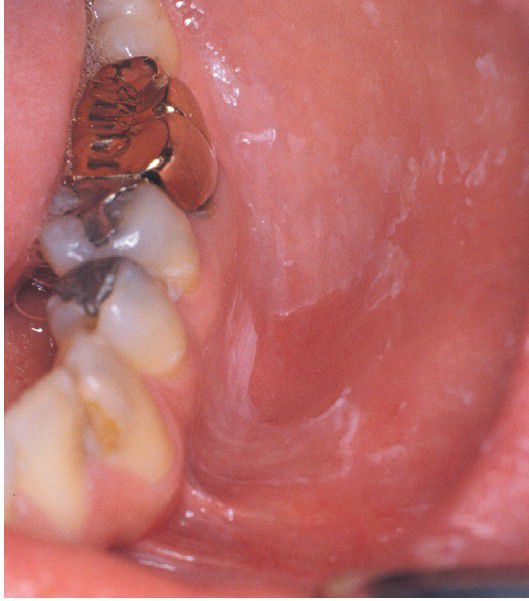

Allergic Contact Stomatitis to Toothpaste.

Erythematous mucosa with superficial epithelial desquamation.